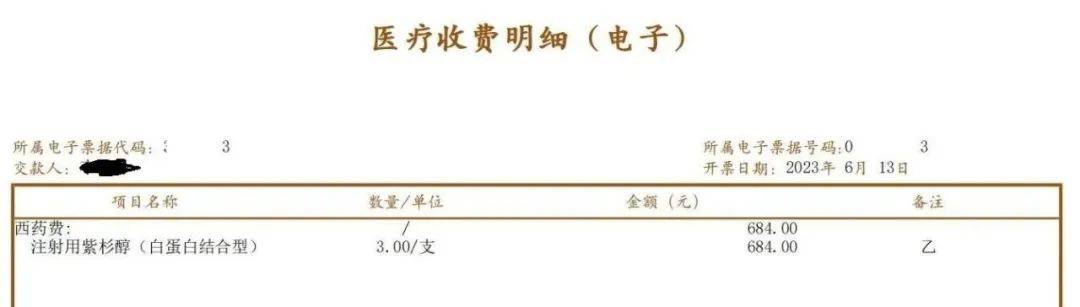

►关于白紫化疗药

紫杉醇(白蛋白结合型)以下简称“白紫”,在2022年国家集采名录里石药的一瓶135元,我爸也享用过。今年复用化疗,第一家医院只有江苏恒瑞的,一瓶736元。经了解,石药白紫一瓶228元,齐鲁的白紫一瓶100多。复用第二次就果断的换了医院,考虑石药做的最早,副反应也小,就用了石药的,一次三瓶省1524元。事后12345投诉第一家医院,医院给回复下次用药可以从第二家医院给我爸调石药的。

其实我的目的是给那些广大有需求的群众省省钱,尤其那些家庭经济困难看不起病的,让大家有个选择,我在哪里都可以用,但是更多的患者家属是两眼一抹黑,他们不知道的。国家政策是好的,落实下来咱也就不多说了。

图片来源:患者提供